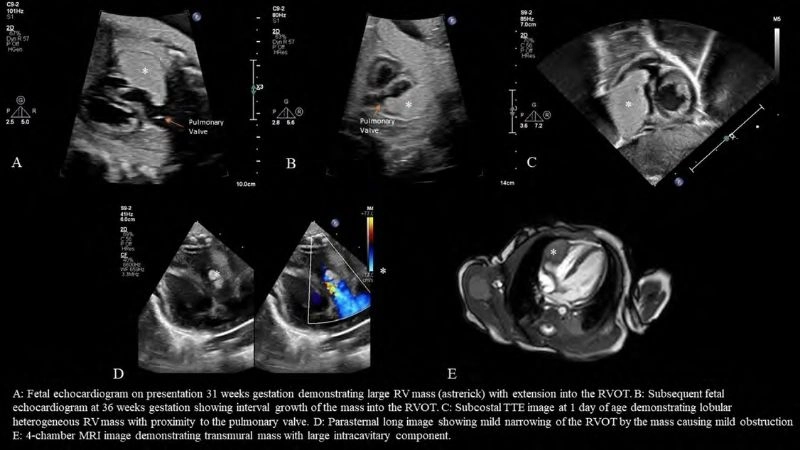

Rhabdomyoma is a rare benign tumor of striated muscle, commonly affecting the heart in children. Images often highlight cardiac masses that disrupt heart rhythm and function.

Insightful capture of fetal rhabdomyoma findings

Real cases of rhabdomyoma in children hearts